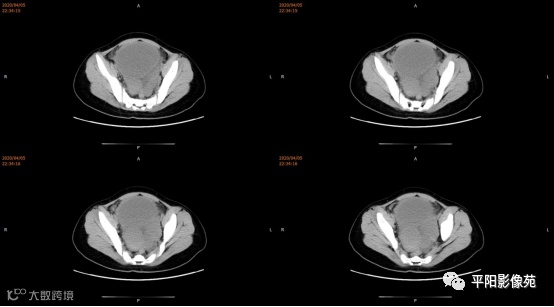

3.CT检查 对子宫、阴道的界限区分有一定限制,对子宫内膜、肌层难以分辨,故CT对子宫先天性异常的研究较少。阴道闭锁时,若宫腔内经血潴留,可见液性低密度聚集,子宫肌层密度均匀。